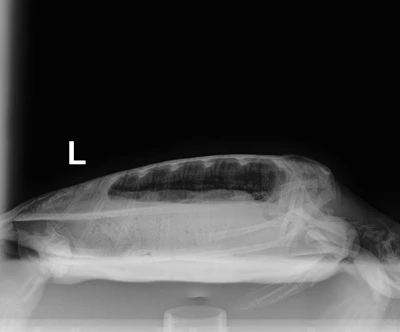

4.55kg juvenile Atlantic Green

Patient Injuries

Flippers: Broken nail on Right rear flipper, Algae build up on soft tissue of rear flippers